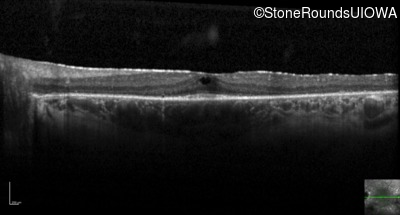

Optical Coherence Tomography - Left - 20/32 -2

Exemplar / OCT Stack

OCT Stack